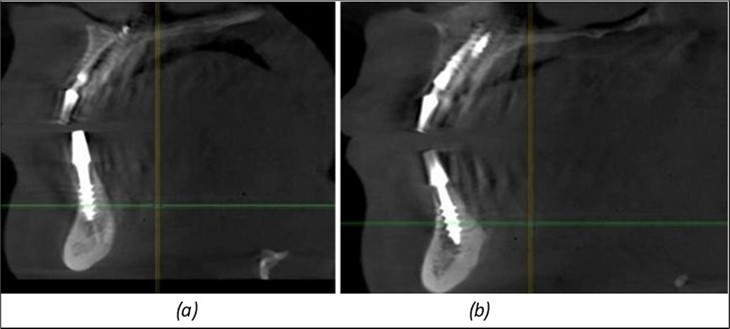

Figure 9.Implants in the pterygoid plateau area: (a) TPG implant fixed in the maxillary-sphenoid junction area, quadrant 1; (b) TPG implant fixed in the maxillary-sphenoid junction area, quadrant 2.

Figure 10.Implants in the palatal sinus cortical area to avoid bone grafting: (a) BCS implant partially fixed in the graft material mass, partially in the palatal cortex; (b) Implant fixed in the palatal cortex at the junction with the nasal cortex, behind the graft material mass.

Figure 11.Implants in the anterior area anchored in the nasal cortex (BCS and TPG): (a), (c) – BCS implants fixed in the nasal cortex; (b), (d) – TPG implants fixed in the second nasal cortex with compression in the trabecular area.

Figure 12.Implants fixed distally in quadrant 4 with fixation at the level of the mylohyoid line: (a) The most distal implant fixed in unaffected bone from the previous restoration; (b) The implant fixed in the area where the two stage implant was removed.